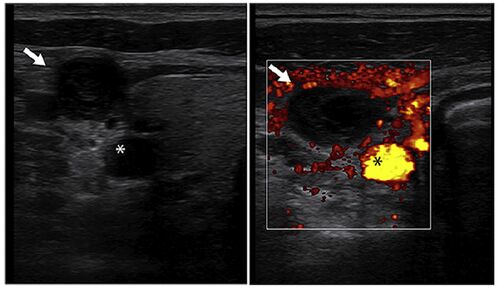

病歴 ・42歳男性 ・失神と頭痛のためER受診 ・BP90/60mmHg、他バイタルサインに異常なし ・ERでも強直間代性痙攣を発症し、自然に停止した 次の一手をどうしましょうか。 痙攣の原因検索として血液検査、心電図検査なんかを行いつつ、CTでしょうか? ・POCUS…